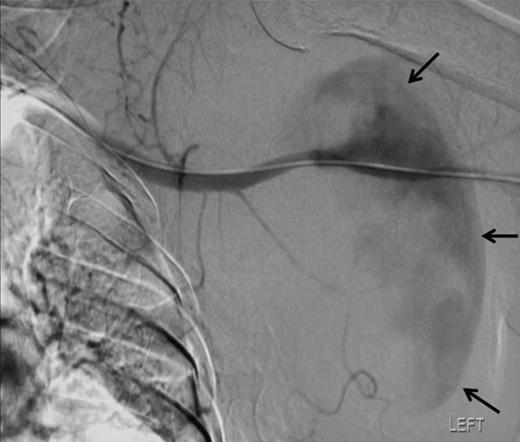

Ten weeks later a repeat orthopaedic review was requested by the rehabilitation team. There had been a slow onset and progression of oedema in the arm, with gradual progression of neurological deficit to the point at which the arm became useless and insensate. An increase in axillary bruising was noted. Also, the patient required a three-unit blood transfusion for a drop in haemoglobin six weeks after the injury. There was a thrill over the whole pectoral region and signs of venous hypertension in the arm. The left radial, ulnar and brachial pulses were normal. Repeat X ray showed subluxation of the left shoulder joint (figure 2). CT angiography revealed a distal axillary pseudoaneurysm with a sac of 15cm diameter (figure 3).

Angiographic localisation of the lesion in the third part of the axillary artery. Please note extravasation of contrast into the sac (arrows)